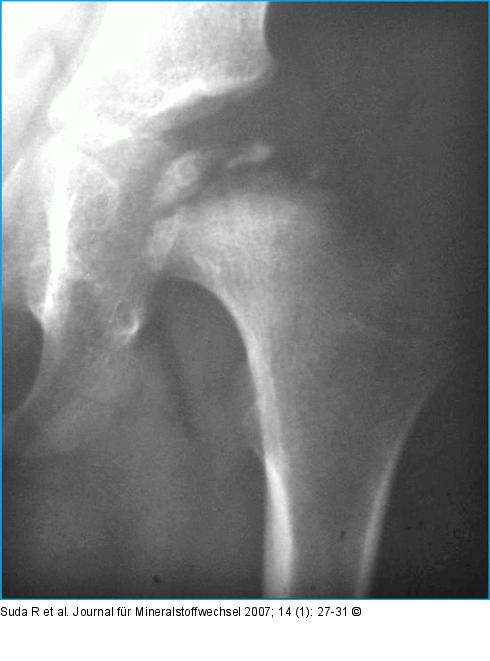

Abbildung 4: Morbus Perthes Morbus Perthes links im Fragmentationsstadium. |

Morbus Perthes links im Fragmentationsstadium. |